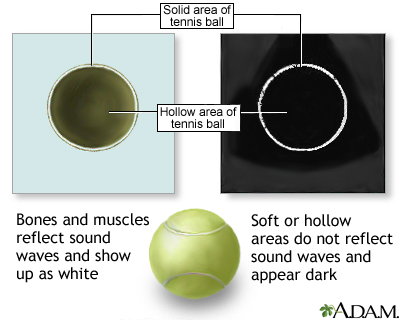

Ultrasound uses high-frequency sound waves to make images of organs and structures inside the body.

An ultrasound machine makes images so that organs inside the body can be examined. The machine sends out high-frequency sound waves, which reflect off body structures. A computer receives the waves and uses them to create a picture. Unlike with an x-ray or CT scan, this test does not use ionizing radiation.